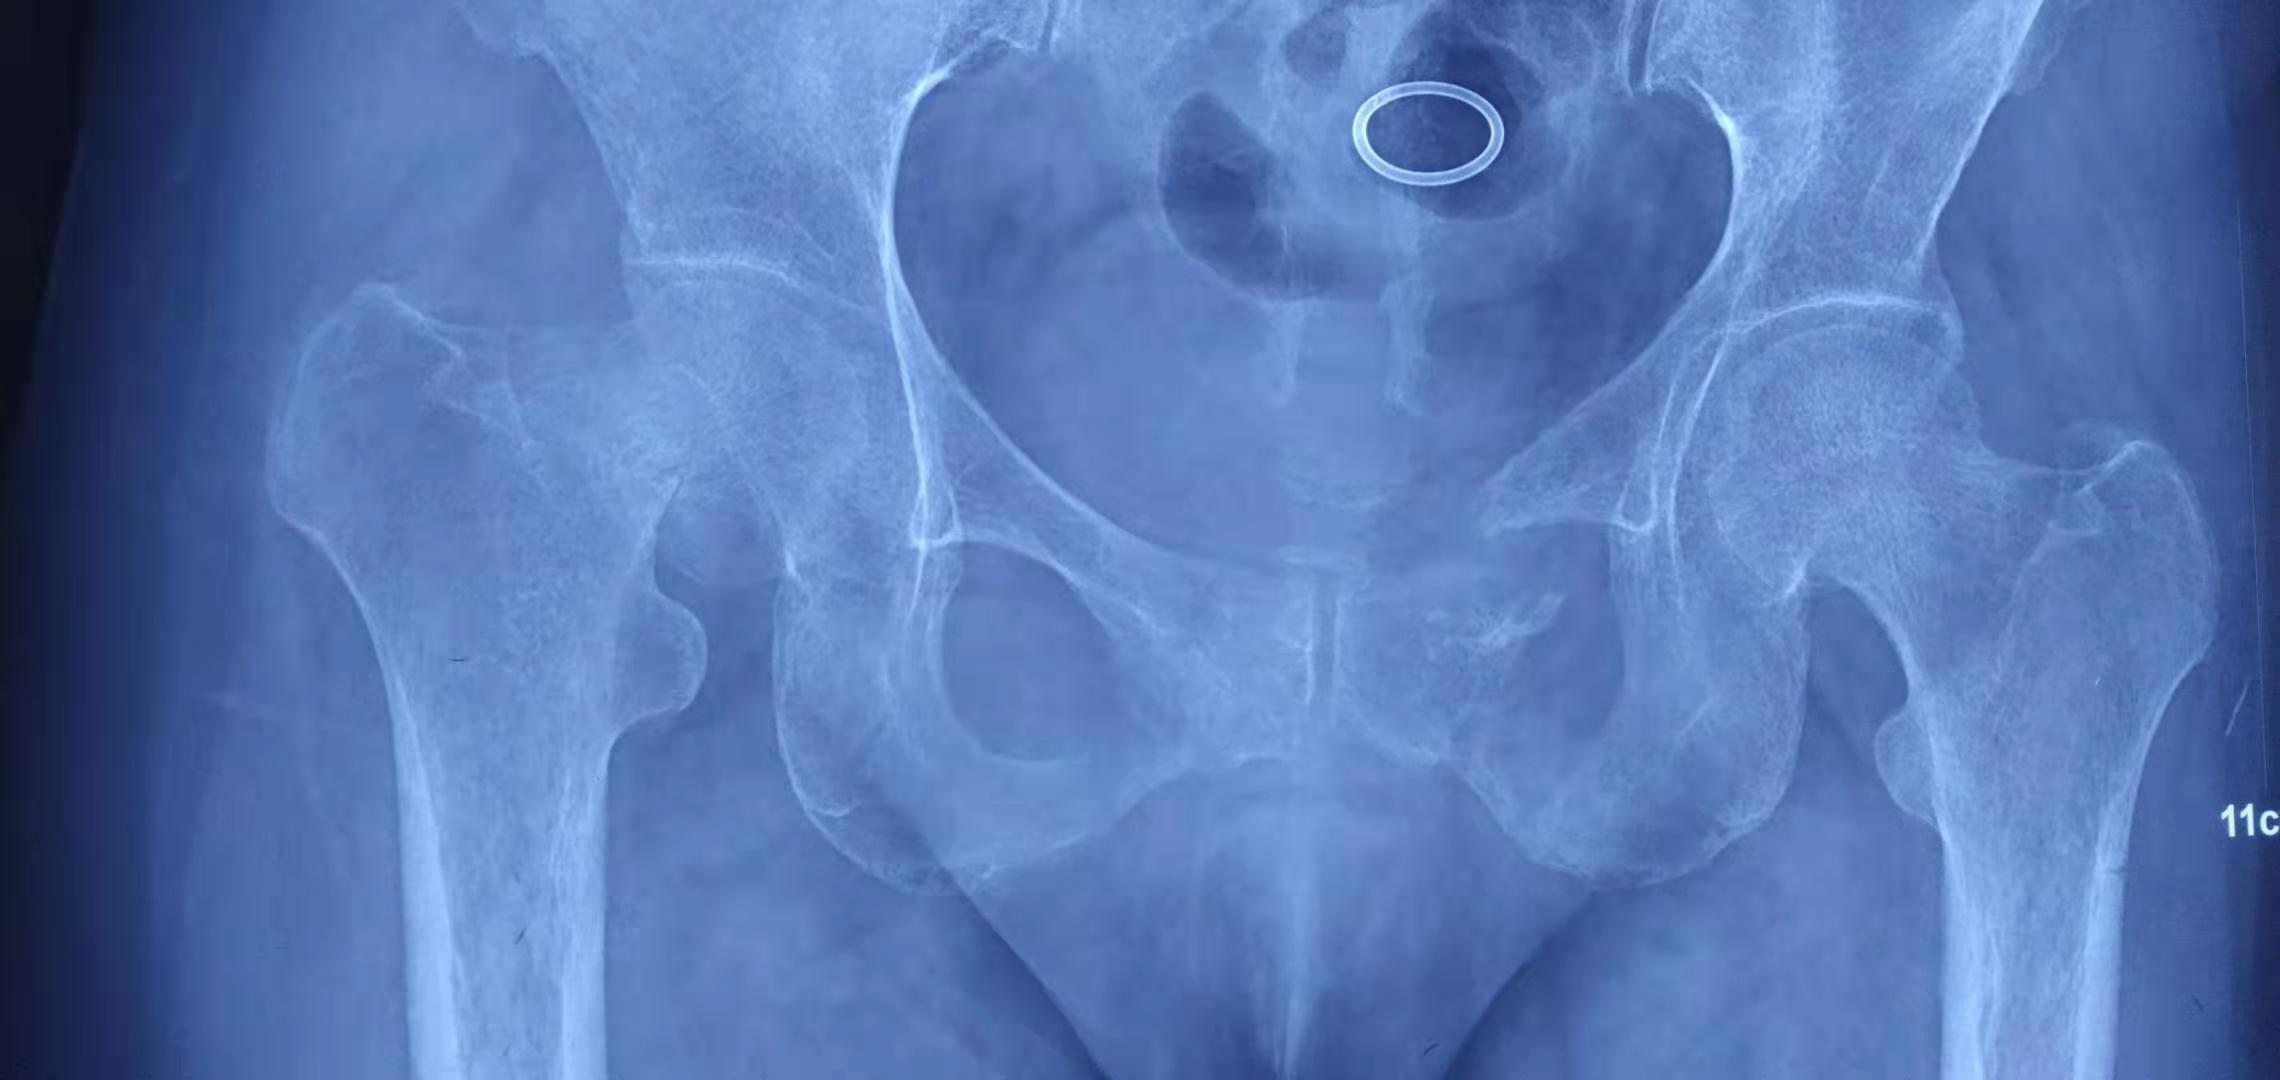

辅助检查:我院全身ECT骨显像+断层:双侧多根肋骨、第7、8、10、11、12胸椎、第1腰椎、左侧耻骨支、坐骨支、耻骨联合、双侧肩关节、肘关节、腕关节、骶髂关节、髋关节、踝关节可见多处放射性浓聚CT定位相可见多处肋骨、肋软骨连接处假骨折。胸腰椎正侧位片示:胸腰段骨质密度减低,骨皮质变薄或皮质线不连续,腰3-5椎体术后改变。骨盆前后位片示:左侧耻骨上下肢骨折,左股骨干上缘外侧皮质刀割样假骨折,右髋关节置换术后改变,腰椎内固定术后改变,右侧耻骨下支骨折。双髋关节CT示:左侧耻骨上下支骨折畸形愈合,右侧耻骨下支骨折,骶骨、左侧股骨颈陈旧骨折改变,右髋关节置换术后改变。曾行全身PET未发现肿瘤。

▼ 双髋关节位片: